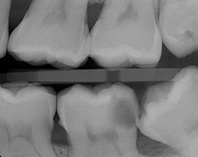

(1.) The use of cold spray on a cotton pellet to perform sensibility testing on tooth No. 8.

Figure 1

Ironically, practitioners currently use relatively low-tech instruments (eg, cold/hot tests, electric pulp testing [EPT]) for sensibility testing to derive complex pretreatment pulpal diagnoses (Figure 1). By definition, sensibility refers to the ability to respond to a stimulus. Thermal and electric pulp tests are considered sensibility tests because they assess the pulp's nerve response to a stimulus. One problem with our current sensibility testing techniques is that they sometimes provide inaccurate results when assessing the real time status of the pulp tissue's state of health.1